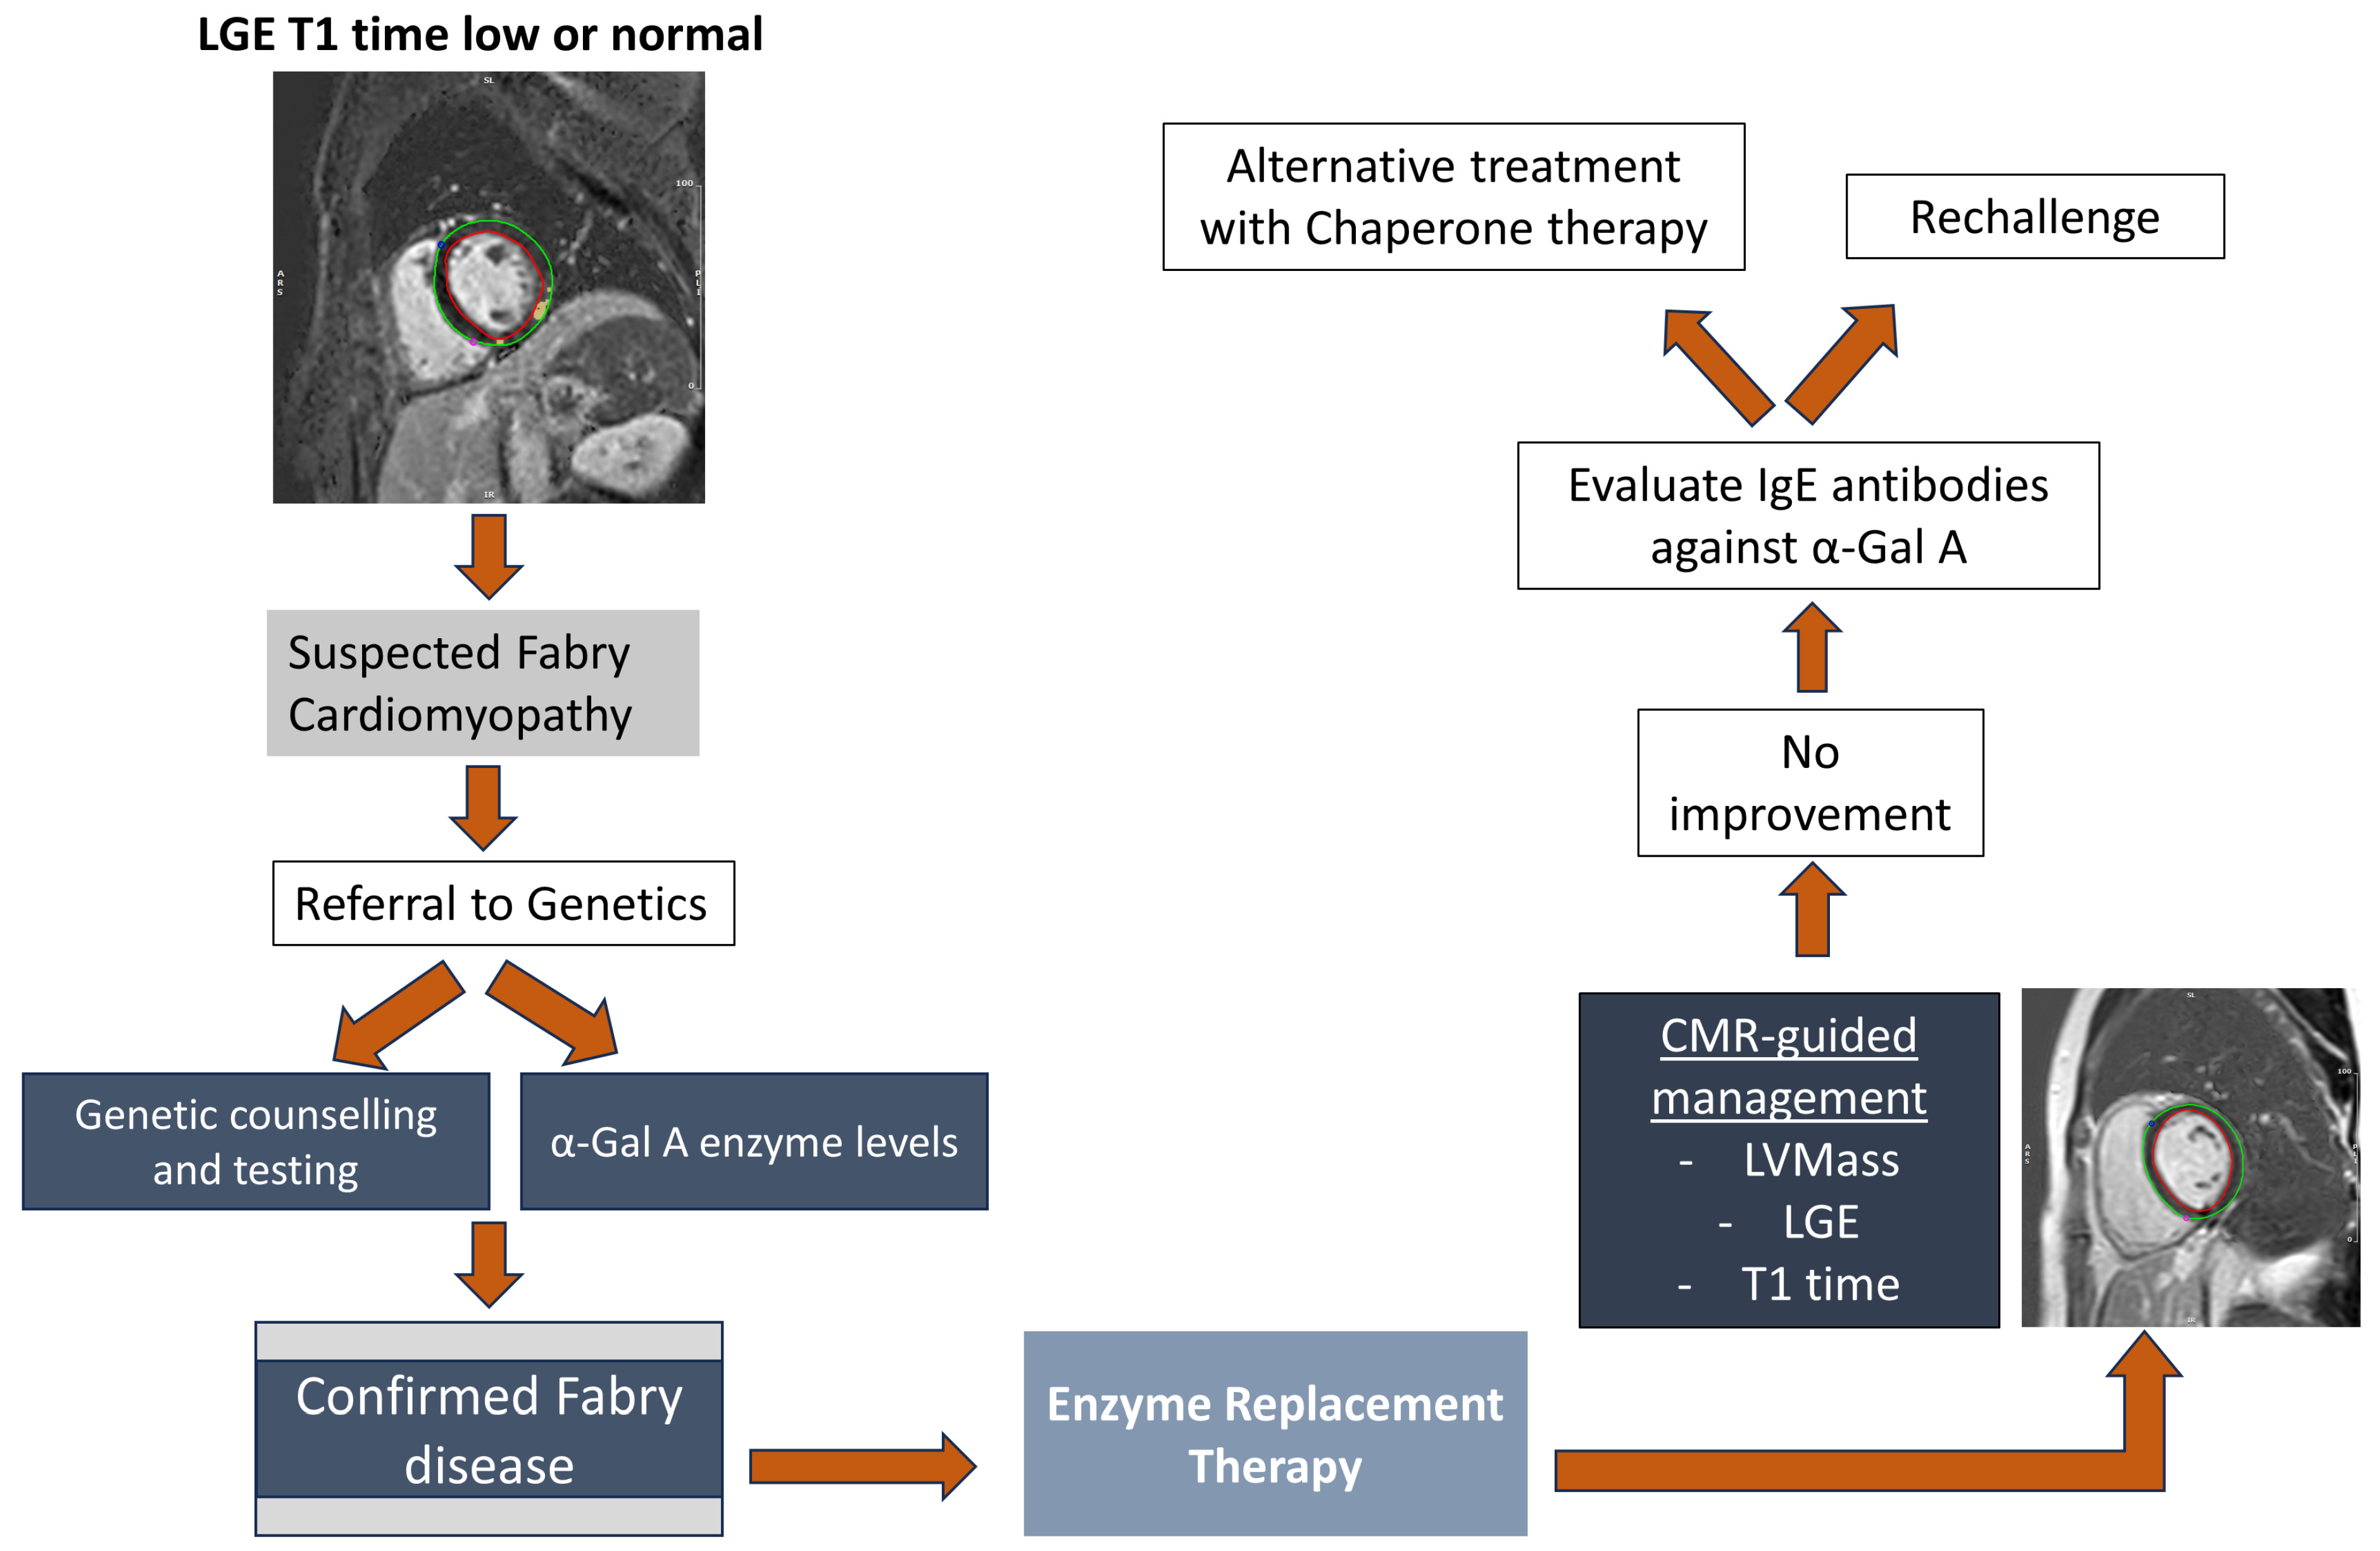

3.3. Cardiac Magnetic Resonance Imaging

4.1. Treatment of Fabry Disease

4.1.1. Enzyme Replacement Therapy

4.1.2. Chaperone Therapy